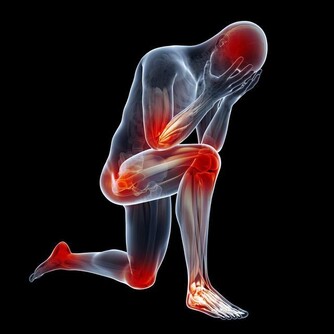

前列腺炎的典型症狀:

1.排尿不適:尿頻、尿急、夜尿多、尿道灼熱感。

2.射精不適:血精、射精痛。

3.局部疼痛:如肛周、下腹部甚至睾丸脹痛。前列腺炎的預防措施很簡單,從病因出發,即可有效預防。